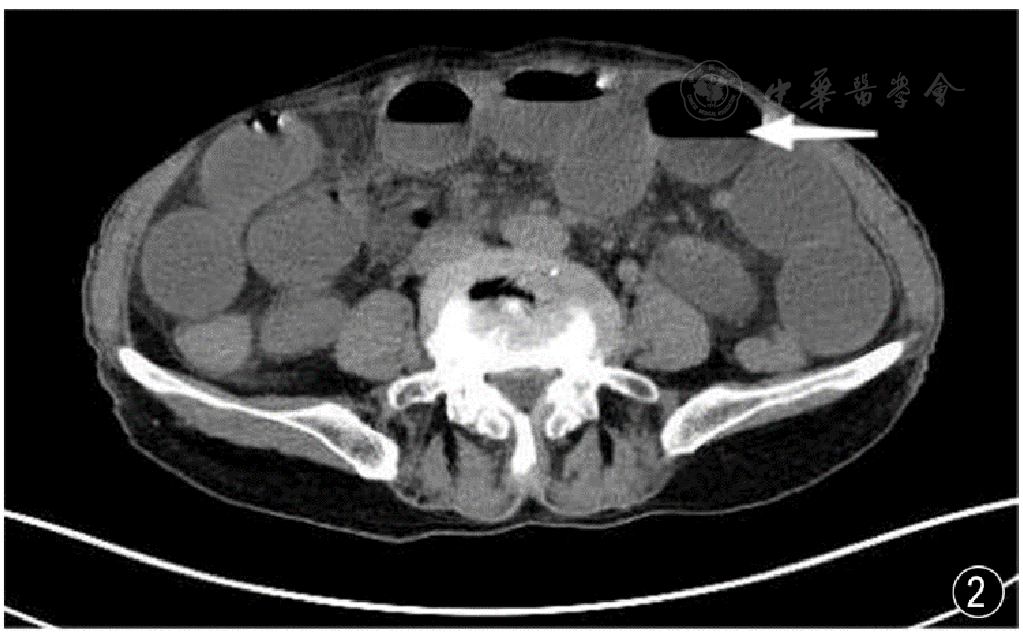

图2 腹腔肠管积气、积液、气液平(箭头所指)